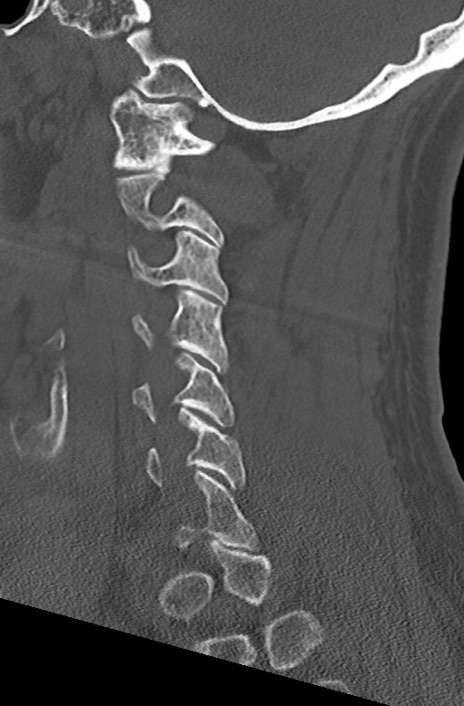

頚椎CT

矢状断像と横断像